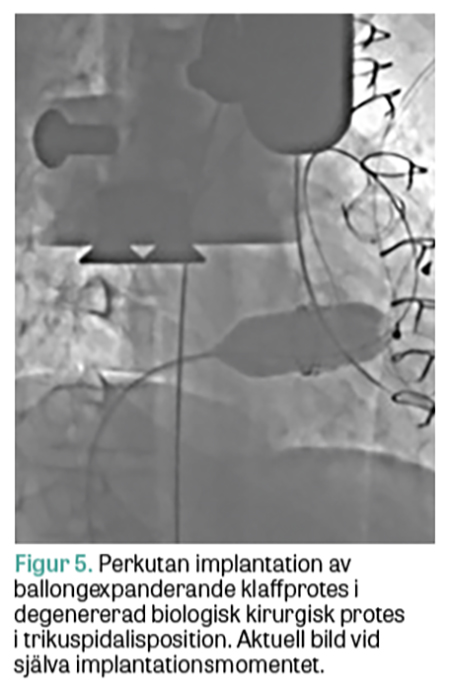

Hos några patienter har man dock noterat en relativt snabb degeneration av inopererade kirurgiska bioproteser, vilket leder till förnyade symtom av hjärtsvikt. Orsaken är troligen en fortsatt hög tumörinducerad hormonaktivitet, trots farmakologisk behandling, som även påverkar klaffproteserna. Dessa patienter kan då kräva ett andra ingrepp där risken med förnyad öppen hjärtkirurgi kan vara alltför stor för att vara rimlig. Kateterburen klaffintervention (transcathether aortic valve implantation, TAVI) är i dag rutinförfarande vid behandling av uttalad aortastenos, men görs även relativt enkelt på patienter med degenererade biologiska aortaklaffproteser (»klaff i klaff«), framför allt kirurgiska, men framgent kan det också förväntas behövas i degenererade TAVI-proteser. Vidare kan kateterburen klaffinplantation göras med gott utfall i degenererade mitralisproteser och i vissa fall även i mitralisringar, men där med sämre resultat [18]. På högersidan ökar erfarenheten av kateterburen klaffimplantation i trikuspidalisproteser och trikuspidalisringar [19], liksom i pulmonalisposition [20, 21]. Det ligger i metodens utveckling att också börja behandla karcinoidpatienterna med degenererade trikuspidalis- och pulmonalisproteser kateterburet, under förutsättning att grundsjukdomen är tillräckligt välkontrollerad. Akademiska sjukhuset i Uppsala bedriver en omfattande verksamhet vad gäller kateterburna klaffinterventioner framför allt mot aortaklaffen, men har en växande erfarenhet av ingrepp mot vitier i andra klaffpositioner. Vi har behandlat ett par patienter med karcinoid hjärtsjukdom med degenererade högerklaffar med kateterburen »klaff i klaff«-implantation (Figur 5 och 6). Med förbättrad onkologisk behandling kan man förvänta sig att gruppen av patienter med karcinoid hjärtsjukdom och degenererade bioproteser kommer att öka. I framtiden skulle patienter med karcinoid hjärtsjukdom som bedöms vara för sköra för traditionell öppen kirurgi teoretiskt kunna erbjudas en primär kateterburen åtgärd, både i trikuspidalis- och i pulmonalisposition.

Figur 5.